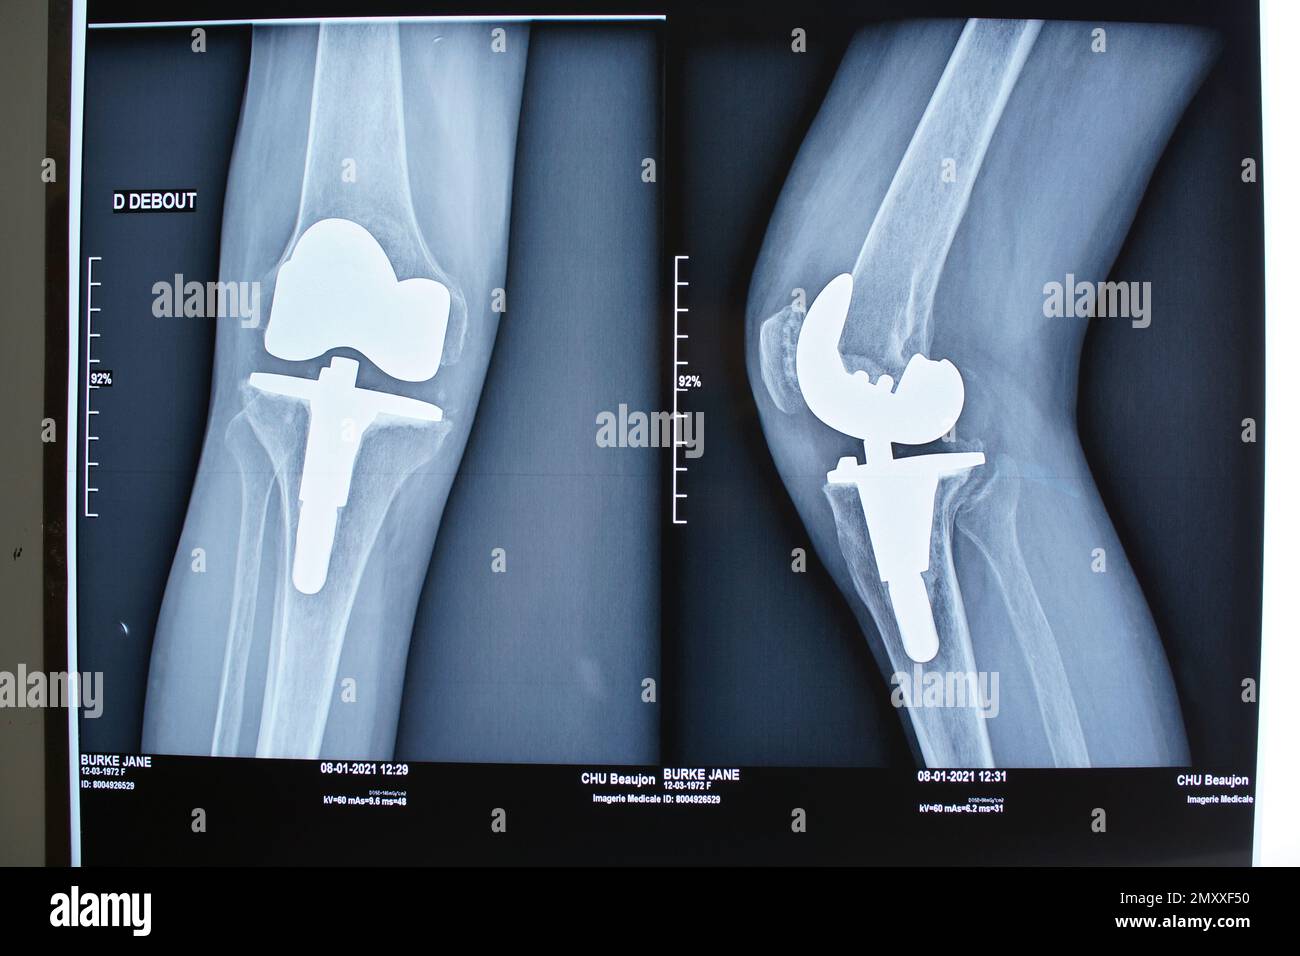

From www.alamy.com

Total knee replacement xray Zimmer NexGen arthroplasty, female Chamfer Cut Total Knee Replacement there are a total of 7 bone cuts in a typical total knee replacement (tkr): there are a total of 7 bone cuts in a typical total knee replacement (tkr): Anterior, posterior & chamfer cuts of distal femur. Distal femur, anterior femur, posterior. surgical technique for tkr. Distal femur, anterior femur, posterior. total knee arthroplasty (tka). Chamfer Cut Total Knee Replacement.